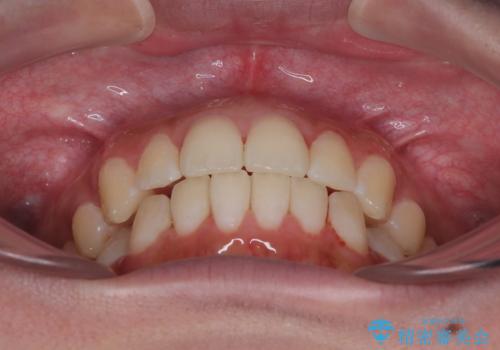

この計画により、デコボコだった下の前歯はしっかりと並び、わずか1年で治療を終えることができました

見た目が気にならないマウスピース矯正だったこともあり、患者様にも大変ご満足いただけました。

見た目を気にせず、効率的に歯並びを整えたい方は、ぜひ一度ご相談ください。